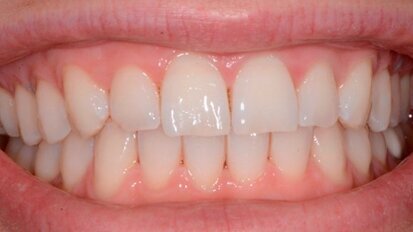

Approccio terapeutico combinato sbiancamento e Infiltrazione Icon della White Spot Lesions (WSL)

La presenza sulle superfici dentali di White Spot Lesions crea disagio nel paziente poiché inficia la bellezza di un sorriso. Il termine White Spot Lesions...